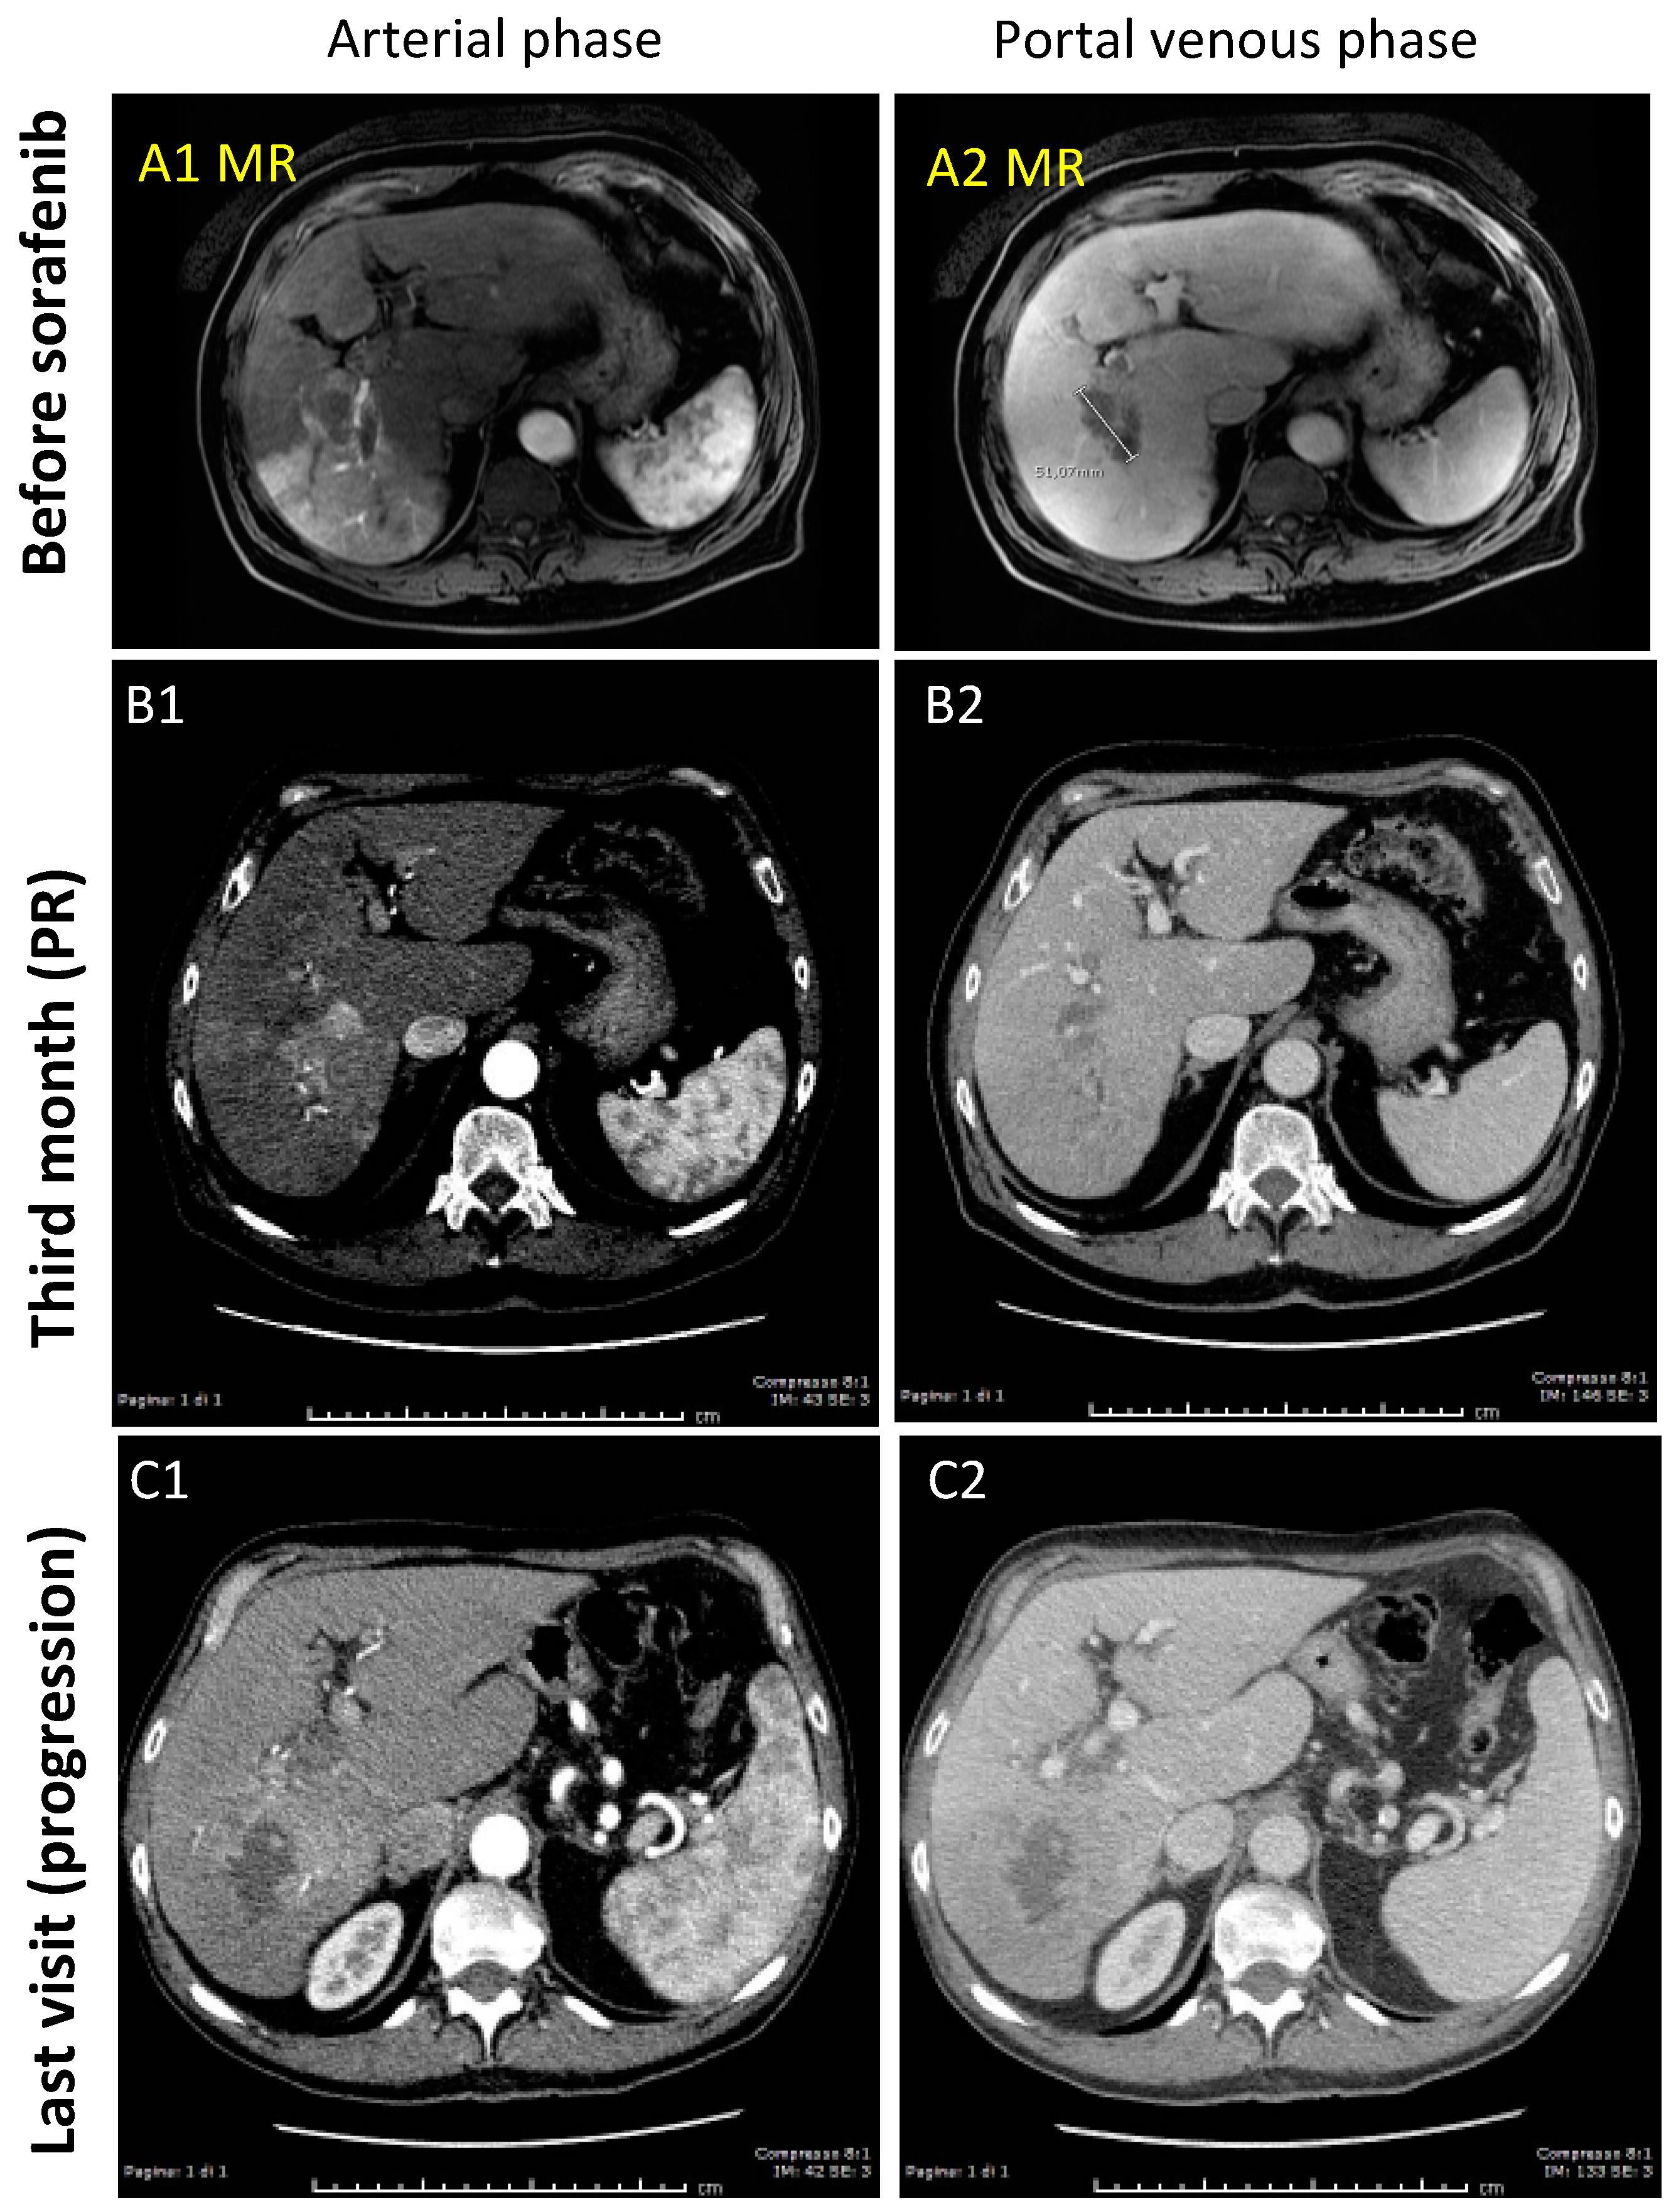

3.1.2. Case-2 (PR to Sorafenib)